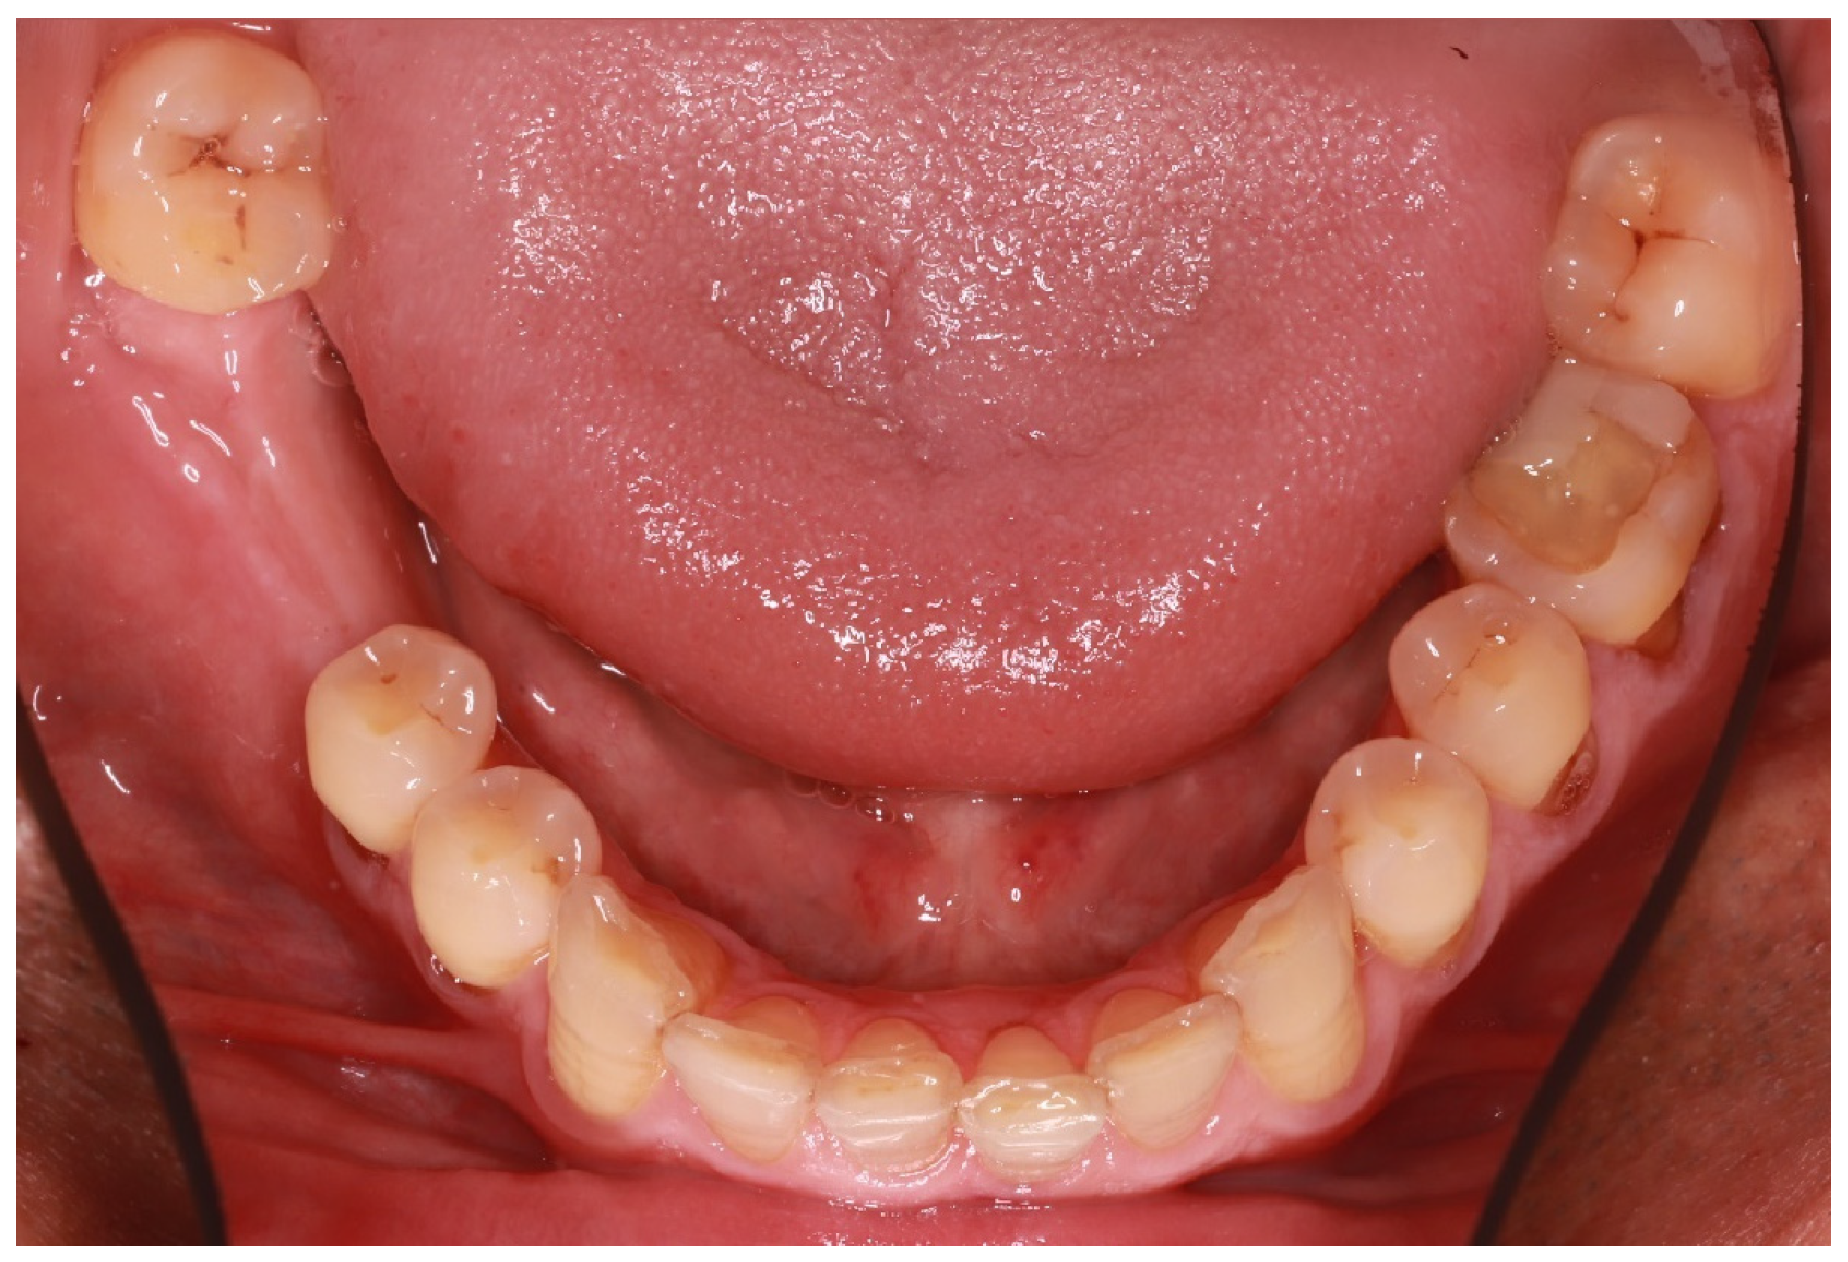

A 57-year-old male patient presented to the XXX Clinic of the XXX University of XXX seeking dental rehabilitation. The chief complaint was the compromised restoration of tooth No. #36 (Figure 1). His medical record did not reveal any disease or medication intake. Clinical examination revealed multiple immediate composite resin restorations with unacceptable morphology and adaptation to the remaining tooth structure as well as lack of contact point but rather a large, concave contact area facilitating food entrapment. After radiographic examination and given that the tooth was endodontically treated and the antagonist was slightly overerupted and limited prosthetic space would be available, the proposed treatment plan included the fabrication of an all-ceramic endocrown. Implant-supported restorations were also proposed for the restoration of missing teeth No. #46 and 47 but due to financial limitations, the patient only wished for the restoration of tooth No. #36 (Figure 1).

Figure 1. Initial situation.